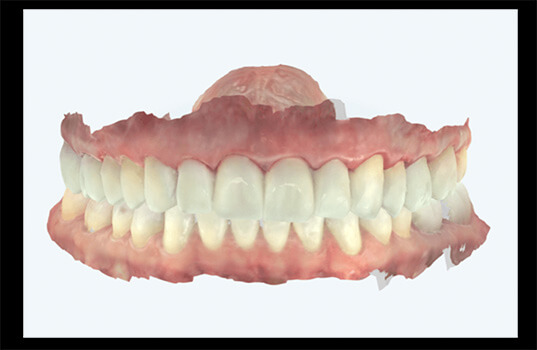

A prototipagem é um processo de fabricação de modelos de dentes ou outras estruturas da boca, geralmente em material plástico ou resina. É usada na odontologia como ferramenta para avaliar e planejar tratamentos, especialmente na ortodontia, prótese dentária e cirurgia bucal.

A prototipagem é realizada com base em imagens radiográficas, modelos de gesso da boca ou outros registros. O material plástico ou resina é moldado para representar a boca do paciente, com seus dentes e outras estruturas. O modelo permite que o dentista ou ortodontista veja o problema em questão e simule diferentes opções de tratamento, antes de realizar qualquer procedimento na boca do paciente.

A prototipagem também é útil para testar ajustes de próteses dentárias, como dentaduras, antes de fabricá-los definitivamente. Além disso, pode ser usada para ensinar pacientes sobre o tratamento que irão receber, ajudando-os a compreender o processo e os resultados esperados.